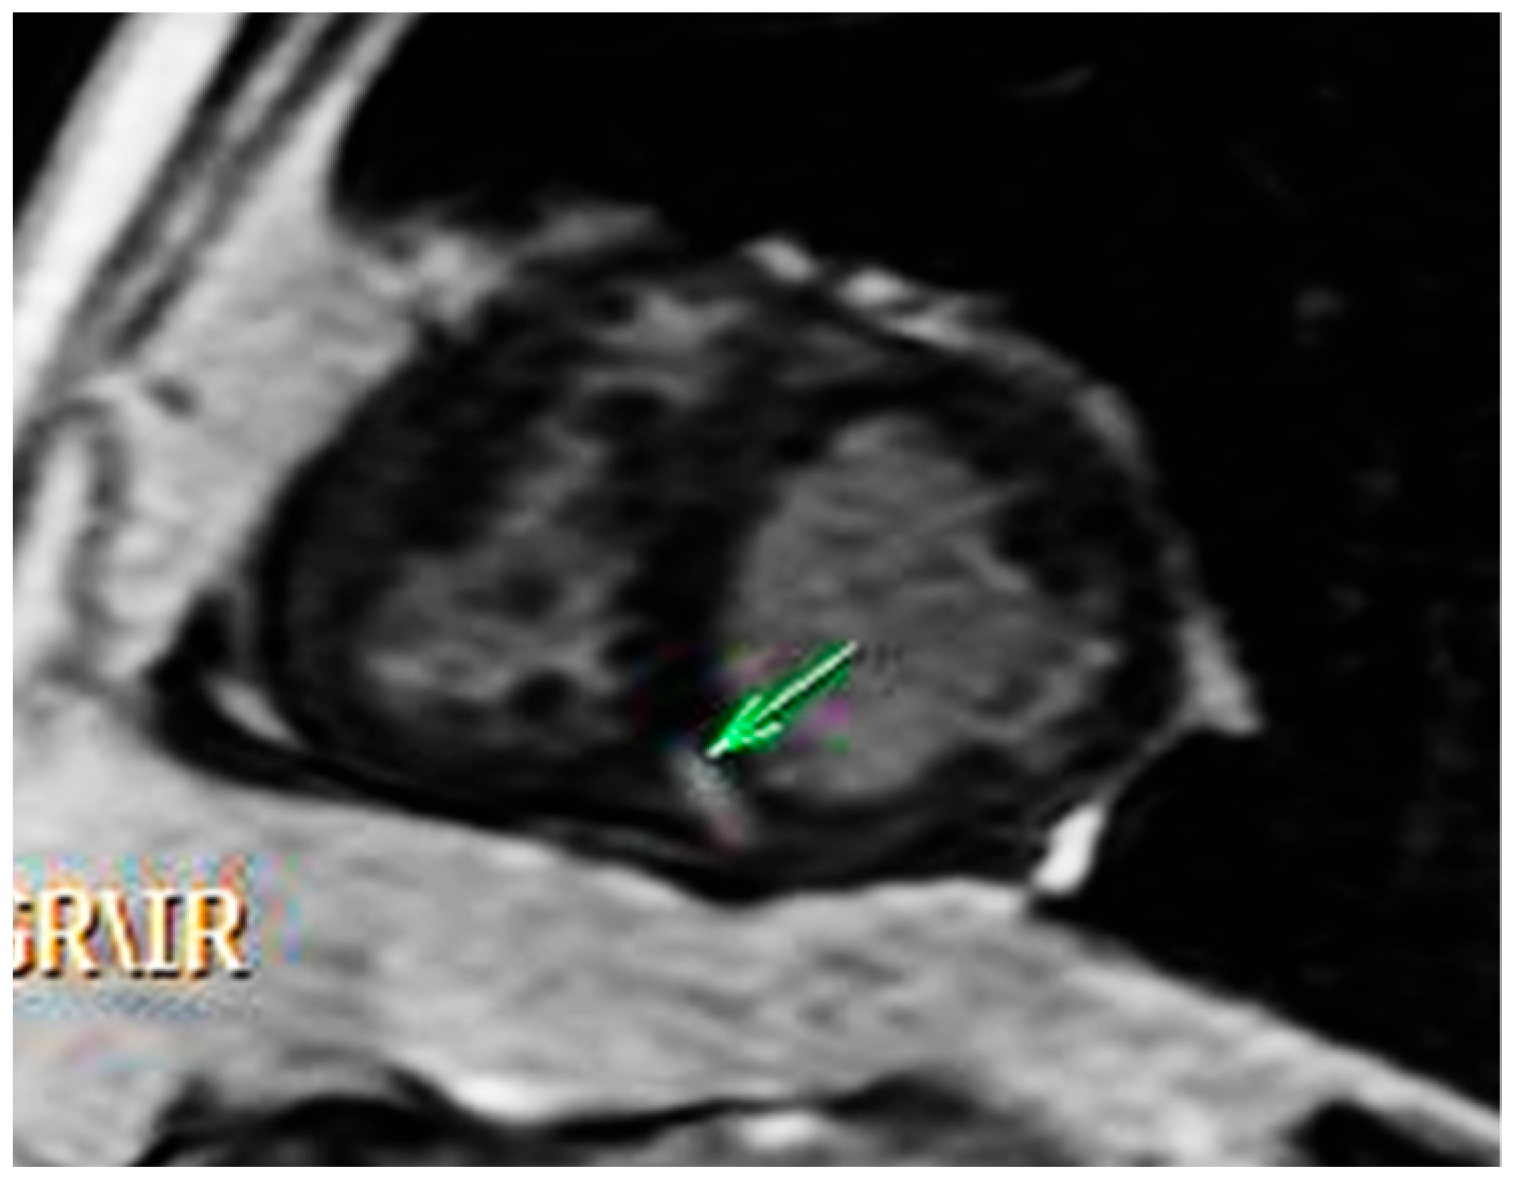

2. Case Report

2.1. Initial Work Up

2.2. Diagnosis and Management